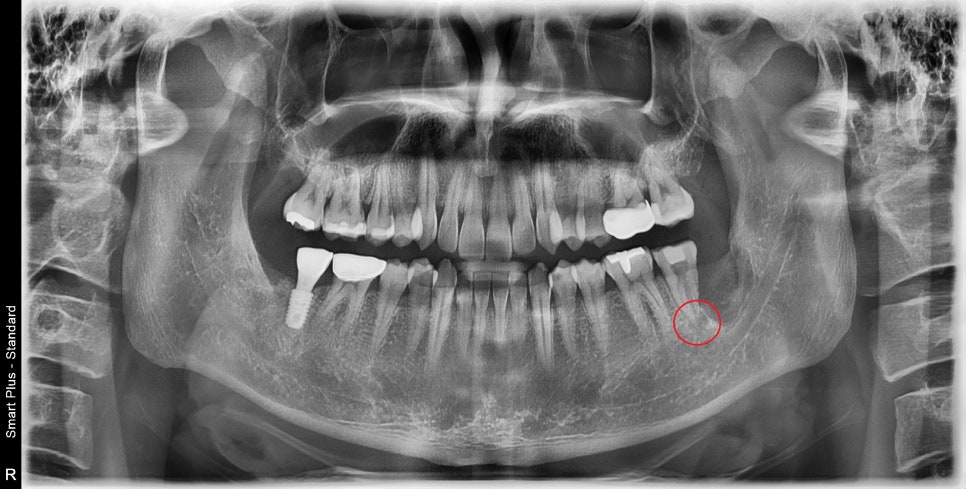

좌측 아래 맨 끝 어금니의 수복물이 떨어져 있습니다.

치아의 맨 끝부분이 깨져나가있으며

엑스레이 상 뿌리끝에 염증 소견이 보입니다.

다른 치아들과는 다르게 뿌리끝이 모아져있는 것을 볼 수 있습니다.